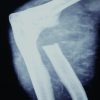

Pre-operative standard knee radiographs were unremarkable, and a scanogram demonstrated normal lower limb alignment (Figs. 1 and 2).

Figure 1: Figure showing normal anteroposterior and lateral view of knee joint.